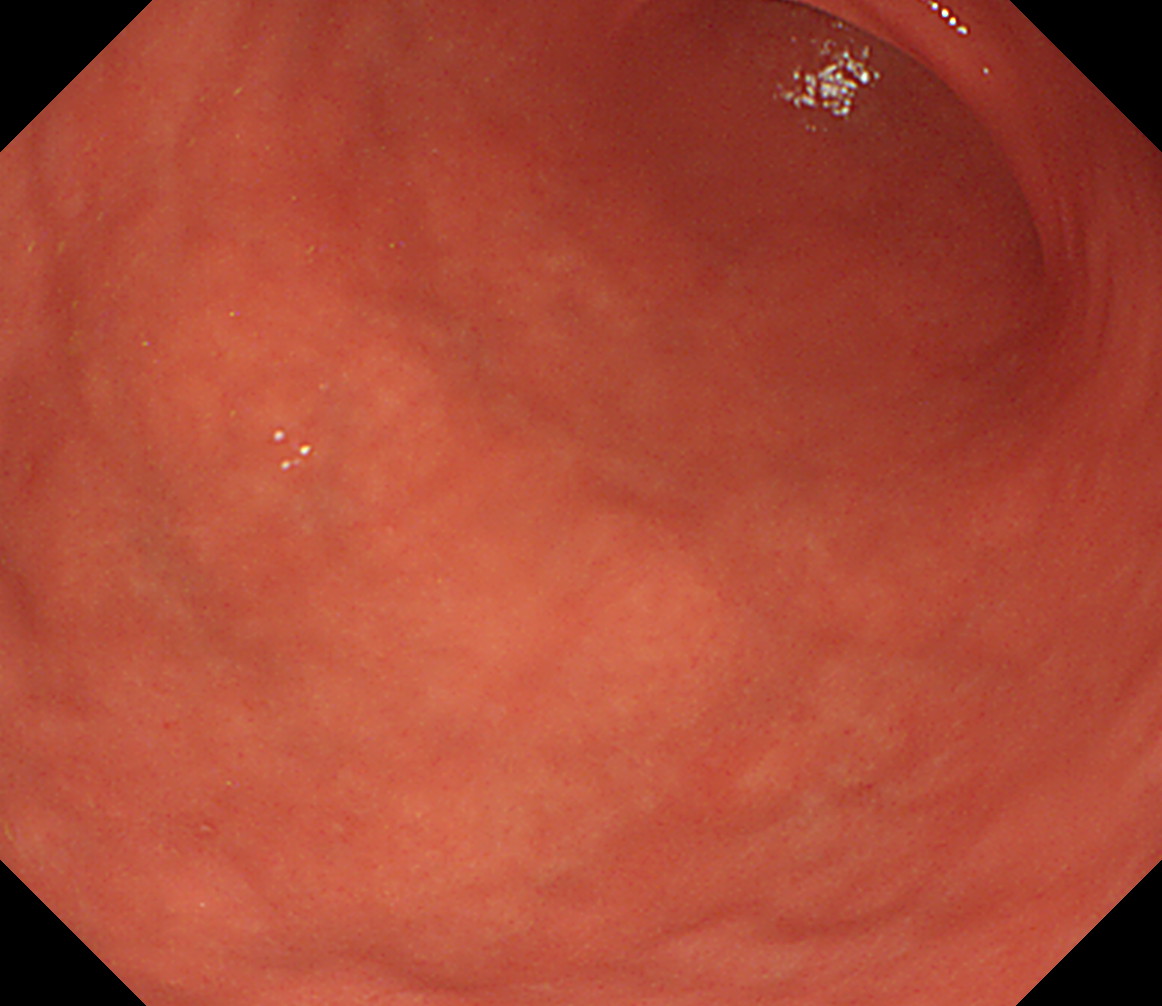

28 体中部後壁 いったんカメラを噴門まで引き上げて胃体中部を決定し

後壁から反時計回り

胃角部大弯